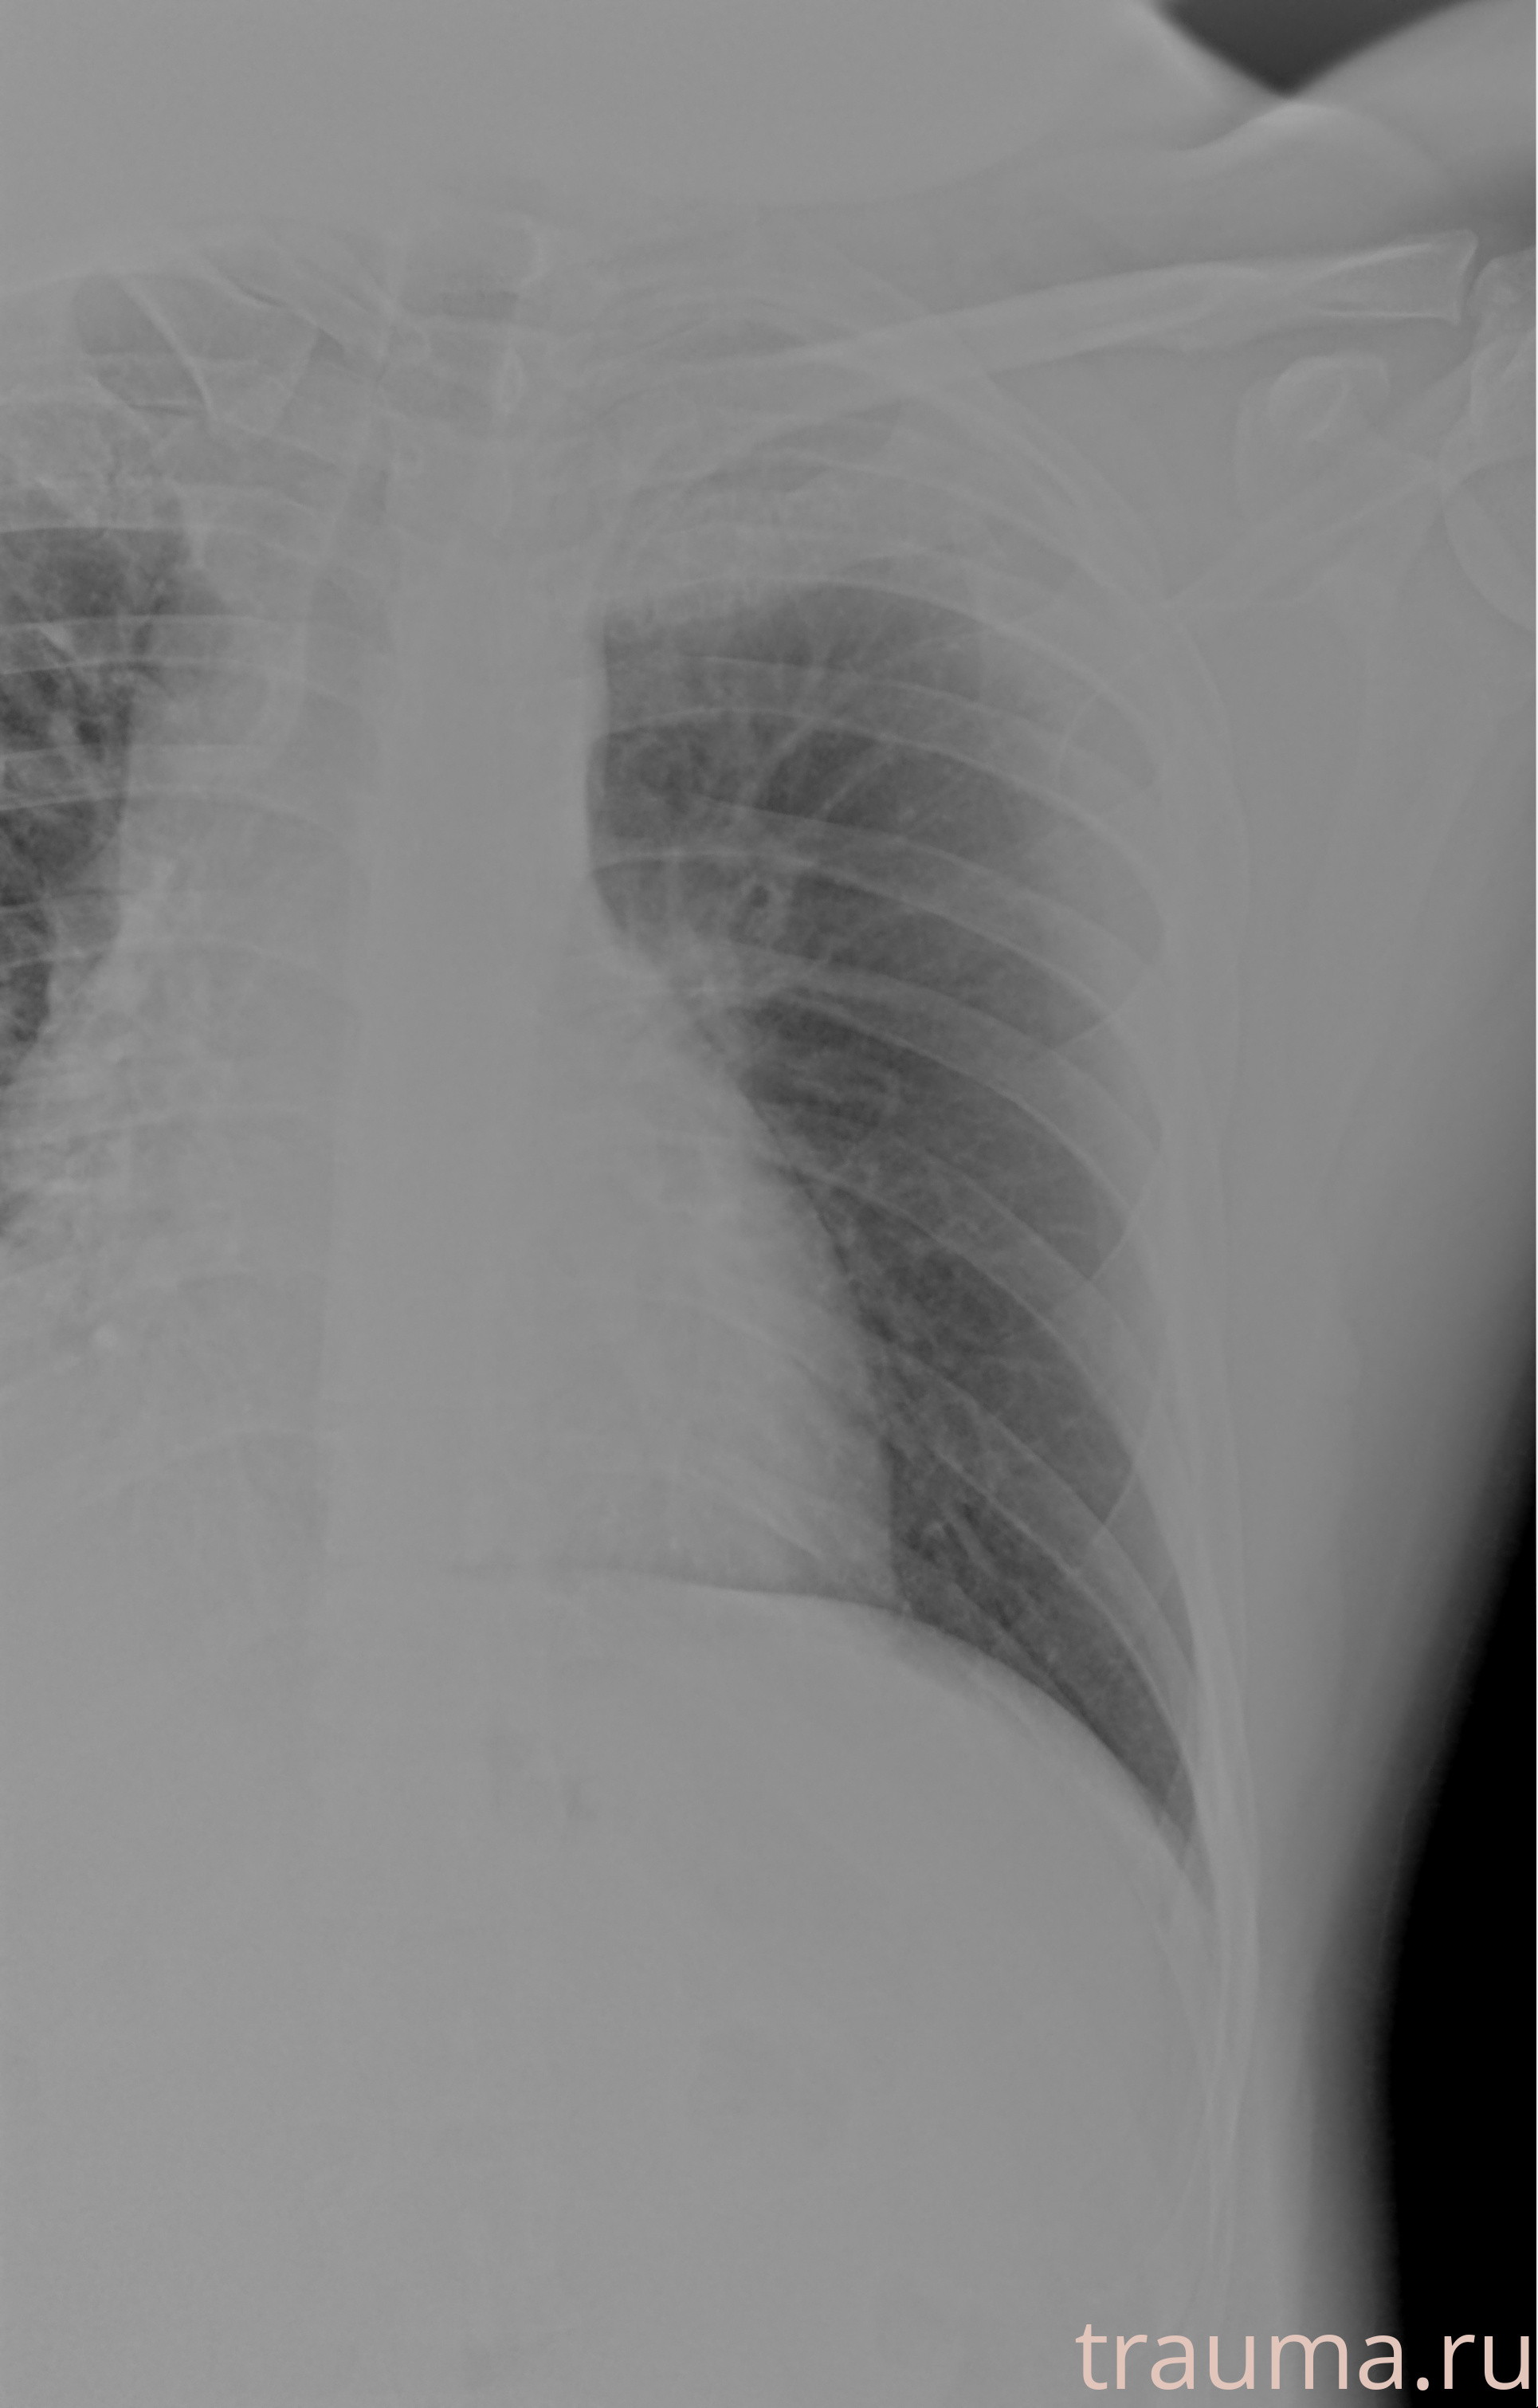

Рентгенограммы

Рентген на дому: по вашему адресу приезжает врач-рентгенолог, травматолог-ортопед с мобильным рентгеновским аппаратом, проводит диагностику травмы или заболевания, делает необходимые рентгенограммы, дает рекомендации по дальнейшему лечению. Получить качественные снимки в домашних условиях возможно благодаря уникальной методике, разработанной МосРентген Центром для института  Склифосовского

Яркость: 1   Контраст: 1   Инвертировать: 0 Увеличение: 1

Перетаскивайте мышь вверх/вниз для контраста, влево/право для яркости. Прокрутка колесом изменяет масштаб. Нажмите Сбросить для возврата к исходному изображению. При увеличении держите мышь в той области, которую хотите рассмотреть.